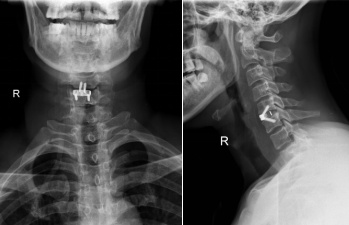

经过积极周密的术前准备,在麻醉科、护理部等的密切配合下,在ICU、输血科等的支持下,徐医生与冯主任联合为患者施行了“颈前路减压植骨融合零切迹内固定术”。由于患者受伤后,软组织肿胀明显,解剖层次不清晰,徐医生克服重重困难,顺利为患者开展手术,术中减压彻底,使用零切迹内固定,避免了传统钢板对食管等压迫造成的异物感。手术切口2cm,术中出不足20ml,历时1.5小时完成手术,真正做到了“微创化手术”。术后患者痛觉过敏及行走不稳明显改善。

术后5天,在康复指导下,患者可自行下地行走去洗手间,双上肢肌力恢复至4级,已能自己使用餐具吃饭,实现生活完全自理。患者及家属对手术效果非常满意,顺利出院。